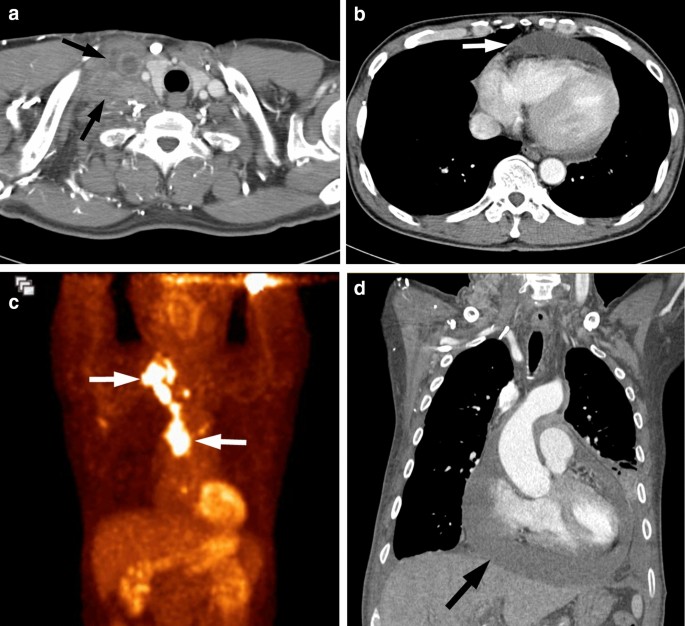

A 44-year-old man with ROS1-rearranged lung adenocarcinoma with pericardial and lymph node metastases. (a, b) Chest CT images demonstrate conglomerated metastatic lymph nodes in the right supraclavicular region (white arrows), which were shown to be metastatic adenocarcinoma from the lymph node core biopsy. Note the moderate amount of pericardial effusion (white arrow), which represents pericardial metastases. (c) Maximum intensity projection image of PET displays intense FDG uptake in the right supraclavicular and mediastinal lymph metastases (arrows). (d) Follow-up CT performed for marked hypotension illustrates an increased amount of pericardial effusion (arrow), which is consistent with impending cardiac tamponade.

CT features of the primary tumor and disease spread patterns according to the three genotypes are summarized in Table 2. Lung adenocarcinomas with ROS1 rearrangement were mainly solid in density (19 of 23, 83%) (Figs. 1, 2 and 3), similar to EGFR-mutant (73%) or ALK-rearranged (88%) tumors, and tended to have a lobulated border (15 of 23, 65%). Compared with EGFR-mutant tumors, ROS1-rearranged tumors were less likely to have air-bronchogram (p = 0.011) and pleural retraction (p = 0.048) but more likely to have pleural effusion (p = 0.025), pericardial metastases (p < 0.001) (Fig. 3B), intrathoracic and extrathoracic lymph node metastases (p = 0.047 and 0.023, respectively) (Figs. 1, 2, 3), and brain metastases (p = 0.017). ROS1- and ALK-rearranged tumors showed similar CT features and no significant differences except for pericardial metastasis, which was more frequent in ROS1-rearranged tumors but statistically insignificant (p = 0.060).